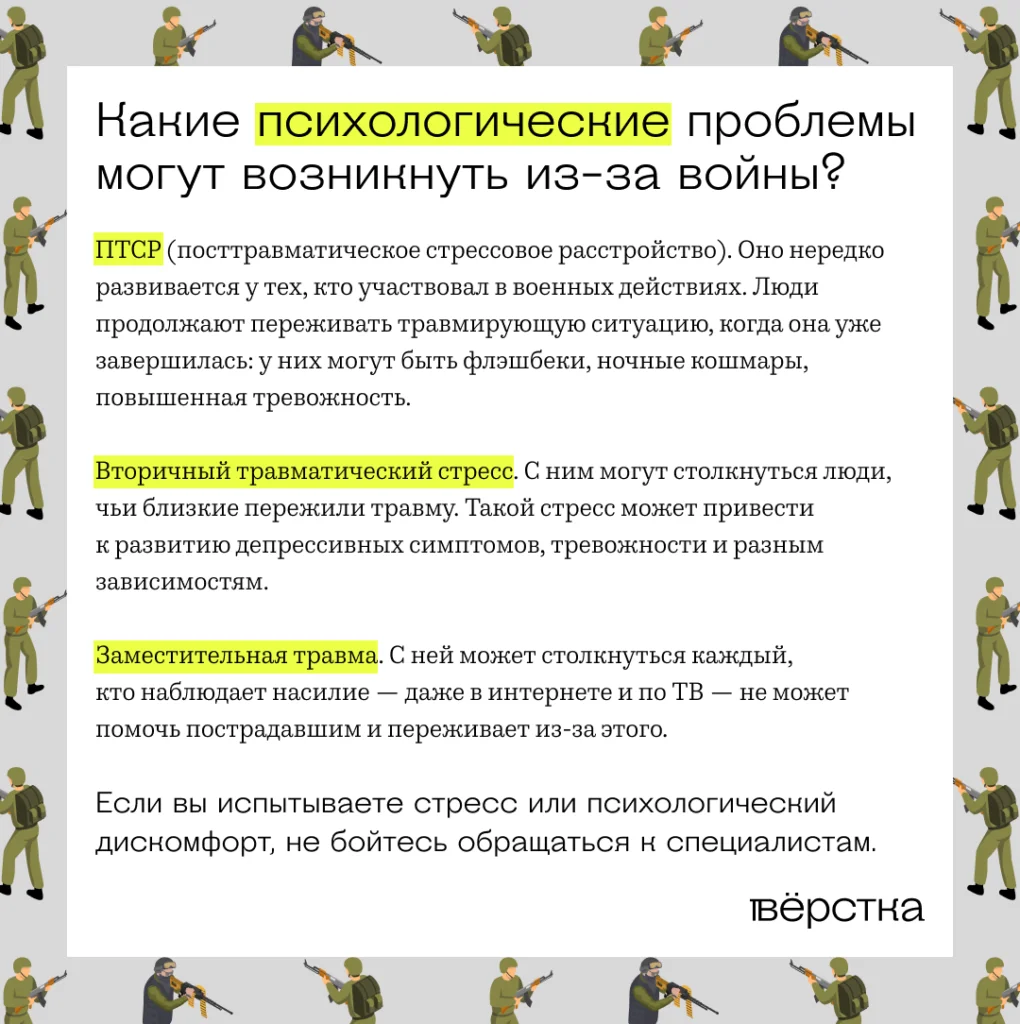

Невозможно сходить на войну и вернуться оттуда тем же человеком, которым ты был раньше. То, что там происходит, слишком сильно отличается от нормальной мирной жизни. Психике нужно адаптироваться к этим условиям, и она делает это по-разному. Поэтому возникают последствия — это может быть и ПТСР, и другие психологические следы.

Но чаще всего, когда говорят о последствиях боевых действий, имеют в виду именно ПТСР — посттравматическое стрессовое расстройство. Это клинический диагноз. Такое расстройство возникает, если психика человека не справилась с каким-либо стрессом. Это могло быть, например, событие, которое угрожало жизни или здоровью. То, что человек переживает в таких ситуациях, — это очень болезненный опыт собственного бессилия.

Травматический след остаётся в тех случаях, когда не хватило поддержки, внутренних ресурсов, рядом не было никого, кто мог бы помочь этот опыт переработать. Можно сказать, что при ПТСР от целостной психики откалывается часть, которая застревает в травмирующем эпизоде и бесконечно проживает этот опыт. Например, человек вернулся с войны, а часть его как будто осталась там. И ей постоянно плохо, больно и страшно.

Даже если человек участвовал в боевых действиях и у него не развилось ПТСР, этот опыт в любом случае меняет его. Могут появиться другие расстройства: депрессивные, тревожные, аддиктивные. Многие чувствуют необходимость заглушать свои эмоции, чувствовать себя дальше от того травматичного опыта, из-за которого они ощутили себя хрупкими и уязвимыми. Часто это делают с помощью алкоголя. Это быстрый и понятный способ в моменте почувствовать облегчение. Но если трезвый человек ещё способен удерживать напряжение внутри себя, то под действием алкоголя или под влиянием триггера его часто прорывает.